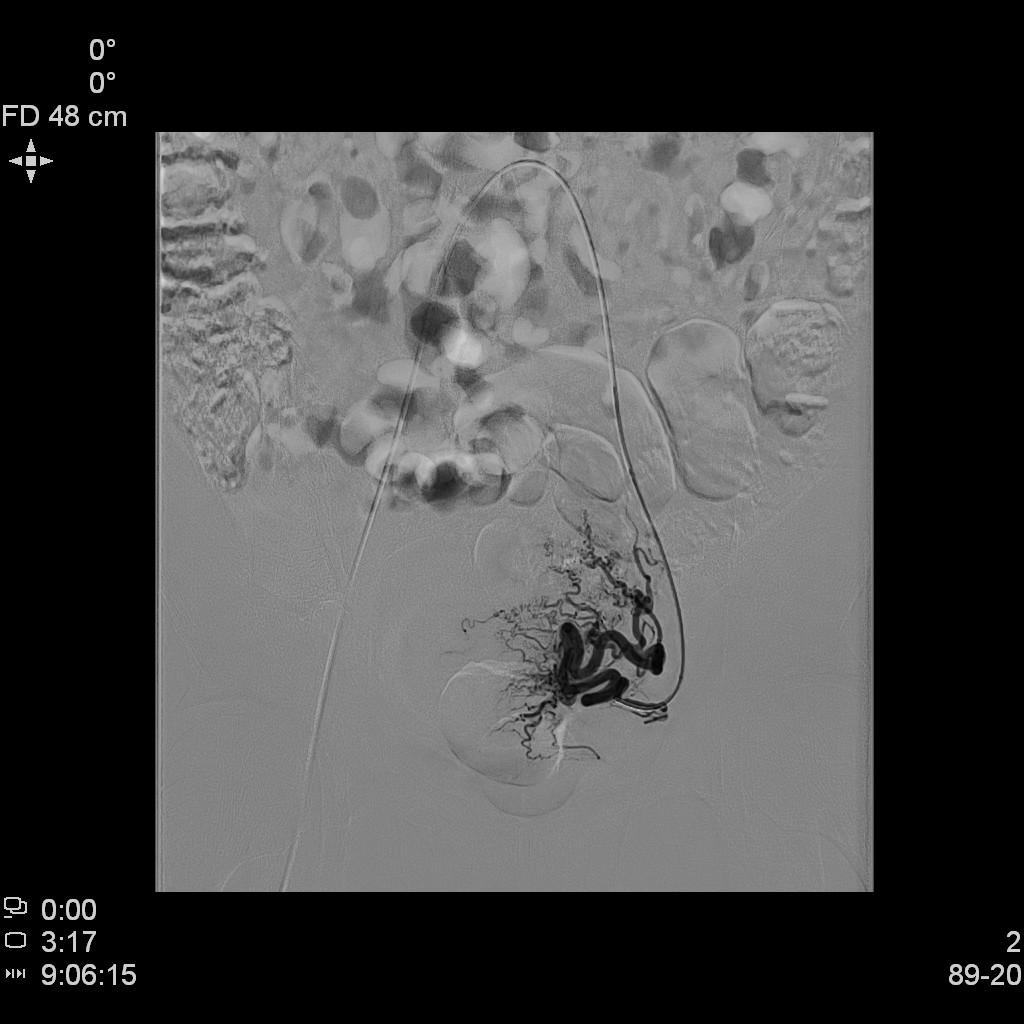

- DSA下行双侧子宫动脉栓塞治疗。

左侧子宫动脉造影

右侧子宫动脉造影

- 经桡动脉入路,分别超选择插管至双侧子宫动脉造影+子宫肌瘤栓塞治疗。